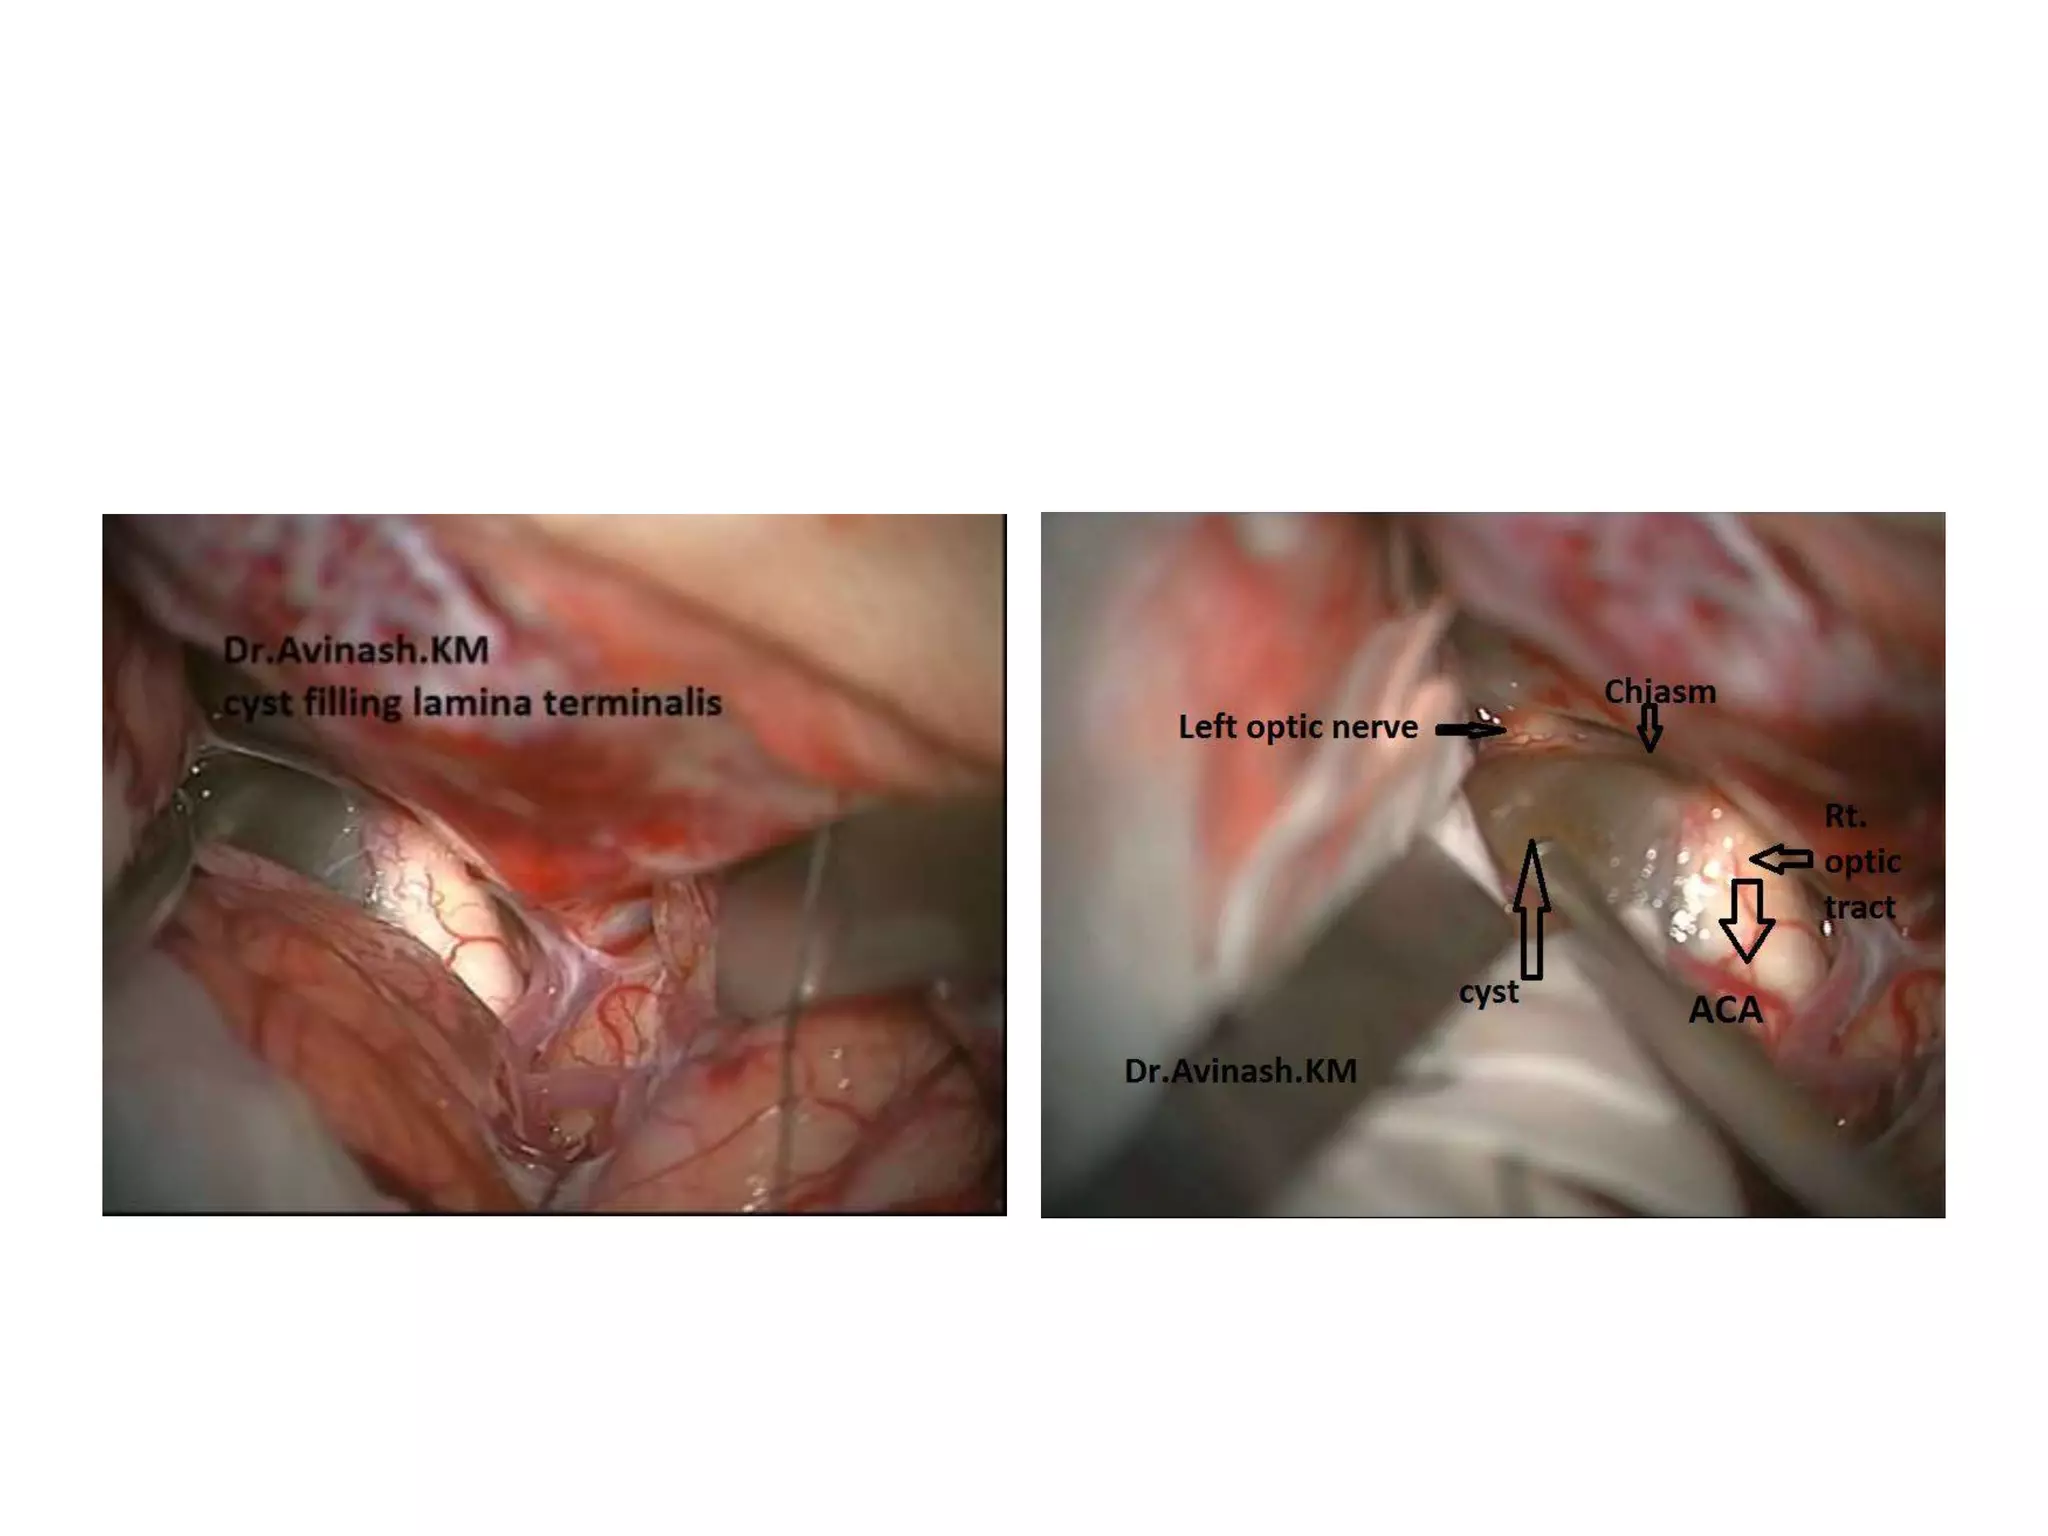

3rd ventricle entry by - Supra optic chiasmic route – by

Lamina terminalis

Recurrent artery of heubner originates

near Acom

3rd ventricle entryby - Supra optic chiasmic route – by Lamina terminalis

• 90.